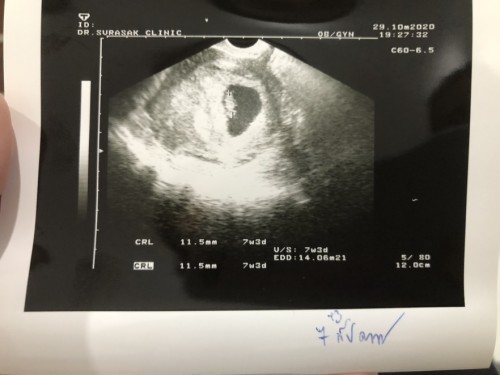

ตามใบซาวด์ 7W3D ถ้านับตามรอบเดือน 8W แบบไหนแม้นฟ้ากันค่ะแล้วจะนับตามแบบไหนดี

ถ้าแม่มั่นใจรอบเดือนว่าไม่ผิดพลาด ก้อนับตามรอบเดือนแม่นกว่าค่ะ